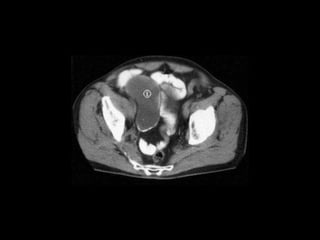

Right ovarian tumor (T)

Right ovarian solido

cystic mass (M)

(T) M